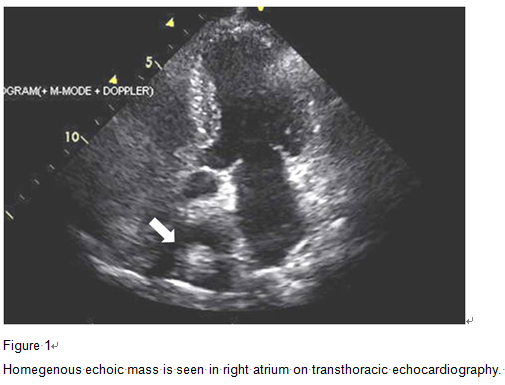

F/73, Incidentally found right atrial mass on echocardiography for evaluation of orthopedic surgery. Previous pulmonary tuberculosis (+), DM (-), HTN (-)

Hwanseok Yong, Korea University Guro Hospital